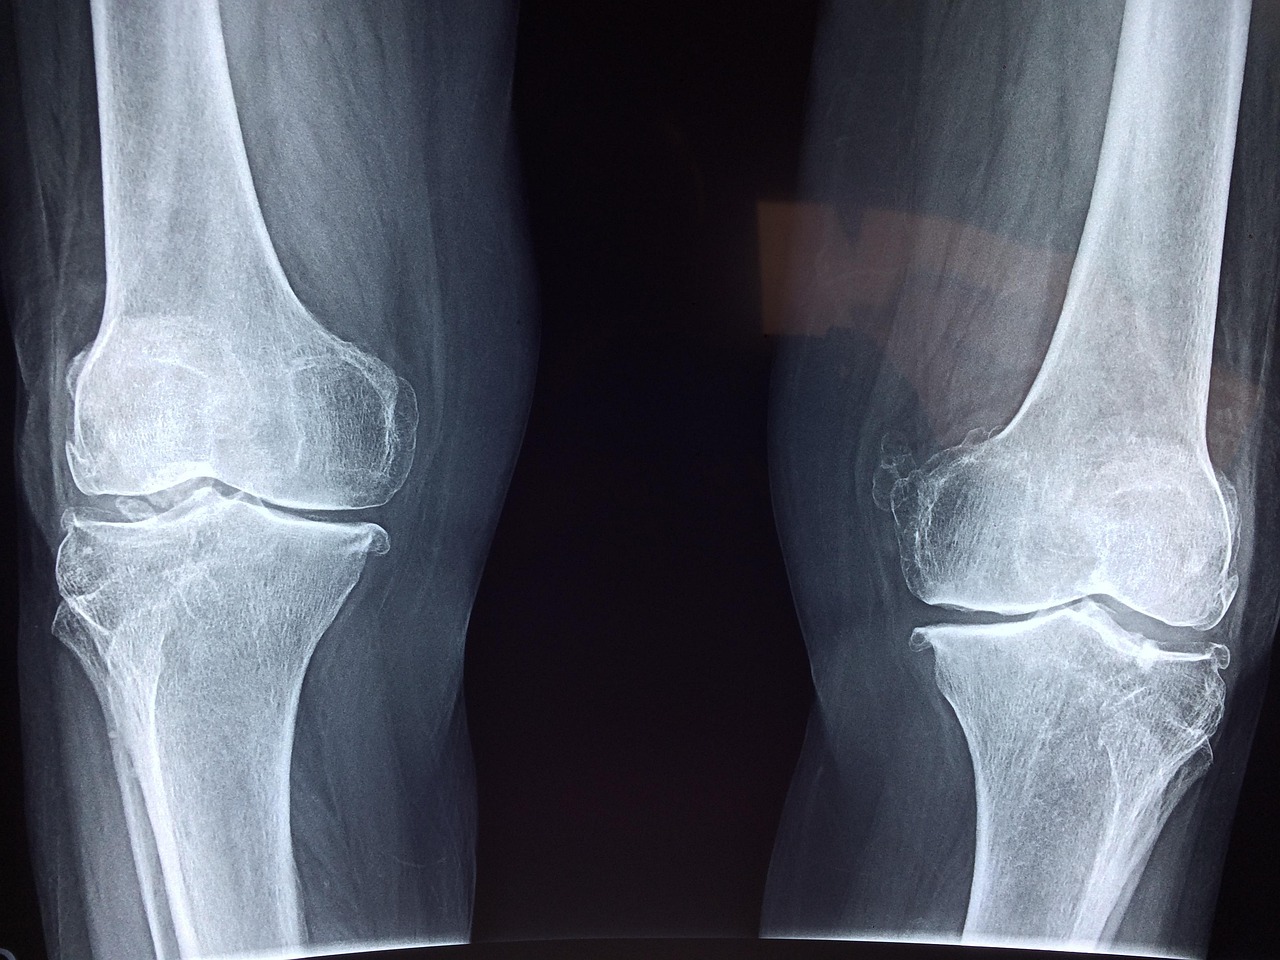

Another key focus of celiac disease awareness should be bone density screening, especially for patients who have been diagnosed later in life. The relationship between celiac disease and bone health indicates that individuals may not exhibit symptoms until significant damage has occurred. Therefore, obtaining a dual energy X-ray absorptiometry (DEXA) scan can provide valuable insight into a patient’s bone density status. DEXA scans help detect early signs of osteoporosis, allowing for timely intervention that can help protect bone health. Healthcare providers should encourage patients to consider periodic screenings, particularly for those with a history of fractures or arthritis. Additionally, understanding the importance of maintaining bone health through diet and lifestyle is essential for individuals with celiac disease and those affected by gluten intolerance. A well-balanced, gluten-free diet rich in calcium and vitamin D should be prioritized. Furthermore, participating in weight-bearing exercises has been shown to strengthen bones and improve overall health in patients. By focusing on prevention and awareness of the risks, individuals can significantly mitigate potential consequences on their bone health associated with celiac disease.